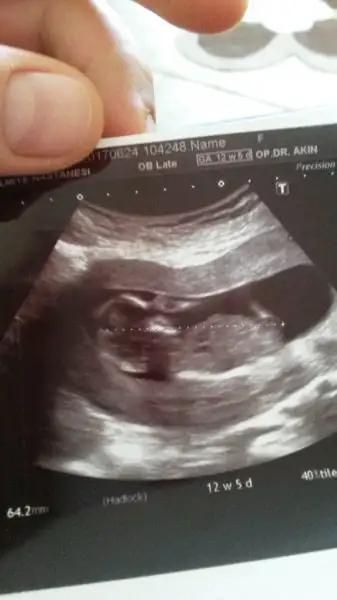

erkek galiba solunda herhalde topigi yanlis anlamadi isem7+1 sizce cinsiyet nedir?

Canım ben erkeğe benzettim bu Ramzi teorisine göre allah gönlüne göre sağlıklı sıhhatli bi evlat nasip etsin inşbenim minigime de bakar misiniz acaba

ck sagoll canmm. allh herseyin hayrlisini versin. onceligim tabiiki sahlikli olmasi ama insan yinede merak ediyorr.Canım ben erkeğe benzettim bu Ramzi teorisine göre allah gönlüne göre sağlıklı sıhhatli bi evlat nasip etsin inş

Arkadaşlar lütfen bi bakın bi yorumlayınn. Çok merak ediyorum.Vajinal usg. Tahminiz nedir. Şimdiden teşekkürler.

Kız gibi canım Rabbim sağlıklı sıhhatli hayırlı evlat nasip etsinArkadaşlar lütfen bi bakın bi yorumlayınn. Çok merak ediyorum.

Çok teşekkür ederim. Sağlıkla sıhhatle gelsin. Bu da 7 haftalık karından usg kız mı acaba gerçektenKız gibi canım Rabbim sağlıklı sıhhatli hayırlı evlat nasip etsin